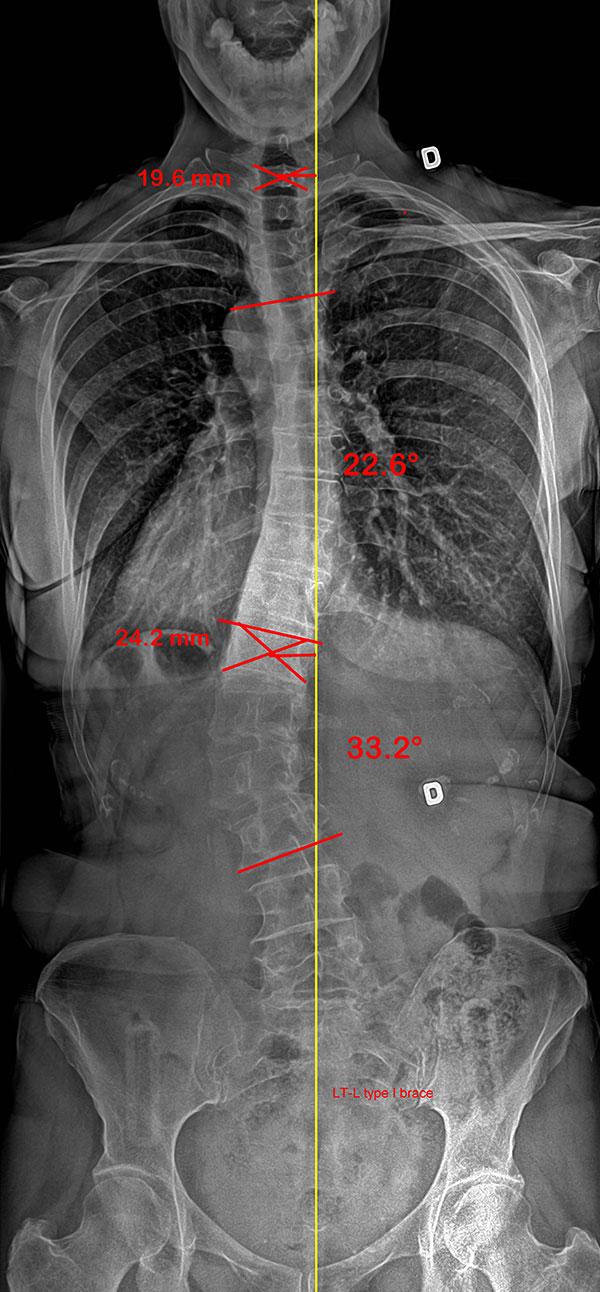

Le cas d'une adolescente âgée de 12 ans et 9 mois (Risser 0) au début du traitement.

Cette jeune fille, dont la photographie montre une difformité importante du dos, souffre d’une scoliose déjà sévère dont la courbe atteint 42° (angle de Cobb) au début du traitement.

Dès l'installation du SpineCor®, on note une réduction de la courbure grâce à l'action dynamique des bandes élastiques malgré une scoliose très importante.

Après 30 mois de traitement, la scoliose est stabilisée à 33° et la croissance terminée. Il est normal avec une courbure d'amplitude aussi marquée de remarquer une légère perte de correction par rapport au premier jour du traitement, car la colonne vertébrale de la patiente a continué de grandir durant le traitement et la courbe d'évoluer. Quand on débute plus jeune le traitement sur des scolioses de moindre amplitude, il est souvent possible d'éviter ces phases d'aggravation.

Mais au final, la dernière photographie prise après le sevrage du traitement montre clairement que la posture de la jeune fille présente un aspect beaucoup plus normal et symétrique qu'au début. Grâce à SpineCor®, l'esthétique de son dos s'en trouve améliorée encore plus que la correction réelle de sa courbe, ce qui aura inévitablement un effet positif direct sur son image de soi.